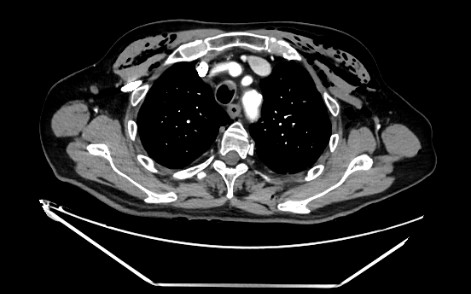

TAC Tórax: fracturas costales 8ª a 11ª, 2 con desplazamiento.

Se confirman laos hallazgos tanto por Rx como TAC Tórax: Fracturas costales izquierdas de 8ª a 11ª con leve neumotórax anteroizquierdo con Atelectasia laminar y opacidades subpleurales izquierdas con Enfisema subcutáneo. Buena evolución posterior con controles periódicos en C.S. con Ecografía Pulmonar.